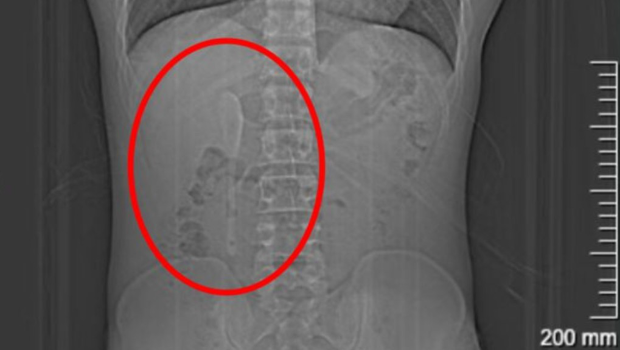

澎湃新闻报道,这名29岁的男子小言(化名),近期因外卖吃出塑料异物前往该院急诊检查。谁知塑料没找到,竟意外发现腹中躺着一支近15厘米长的咖啡匙羹。CT显示,这支匙羹横亘于十二指肠的狭窄处,稍有不慎即可能刺穿肠壁,引发腹膜炎或大出血。